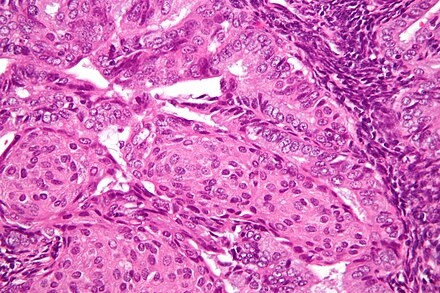

Ki-67 is positive in single tumor cells (<1%). Conclusion: ESS of low grade of malignancy (G1), therapeutic pathomorphosis is not expressed (fig. 2, on the color insert). Figure 2. Histological structure of endometrial stromal sarcoma. Stained with hematoxylin and eosin. ×400. At the control examination 3 months after the operation, there were no signs of continued tumor growth.